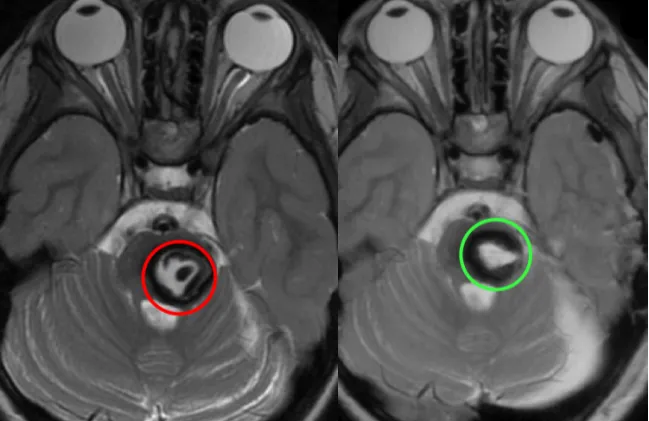

L同學(xué)顱腦MR顯示中腦占位,混雜信號(hào),海綿狀血管瘤可能。

圖:L同學(xué)顱腦MR顯示中腦占位,混雜信號(hào),海綿狀血管瘤可能。

術(shù)后即復(fù)查顱腦MR顯示病變?nèi)?,無(wú)腦水腫、出血等,瘤腔內(nèi)高信號(hào)灶是止血材料(紅色術(shù)前,綠色術(shù)后)。

圖:術(shù)后即復(fù)查顱腦MR顯示病變?nèi)?,無(wú)腦水腫、出血等,瘤腔內(nèi)高信號(hào)灶是止血材料(紅色術(shù)前,綠色術(shù)后)。